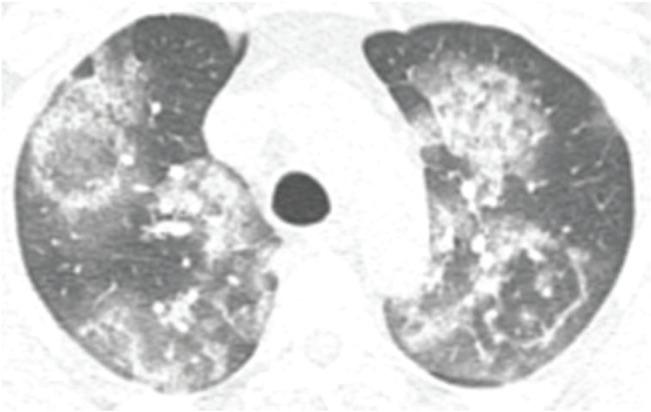

The coronavirus disease (COVID-19), caused by the severe acute respiratory syndrome coronavirus 2 (SARS-CoV-2), emerged in Wuhan city and was declared a pandemic in March 2020. Although the virus is not restricted to the lung parenchyma, the use of chest imaging in COVID-19 can be especially useful for patients with moderate to severe symptoms or comorbidities. This article aimed to demonstrate the chest imaging findings of COVID-19 on different modalities: chest radiography, computed tomography, and ultrasonography. In addition, it intended to review recommendations on imaging assessment of COVID-19 and to discuss the use of a structured chest computed tomography report. Chest radiography, despite being a low-cost and easily available method, has low sensitivity for screening patients. It can be useful in monitoring hospitalized patients, especially for the evaluation of complications such as pneumothorax and pleural effusion. Chest computed tomography, despite being highly sensitive, has a low specificity, and hence cannot replace the reference diagnostic test (reverse transcription polymerase chain reaction). To facilitate the confection and reduce the variability of radiological reports, some standardizations with structured reports have been proposed. Among the available classifications, it is possible to divide the radiological findings into typical, indeterminate, atypical, and negative findings. The structured report can also contain an estimate of the extent of lung involvement (e.g., more or less than 50% of the lung parenchyma). Pulmonary ultrasonography can also be an auxiliary method, especially for monitoring hospitalized patients in intensive care units, where transfer to a tomography scanner is difficult.